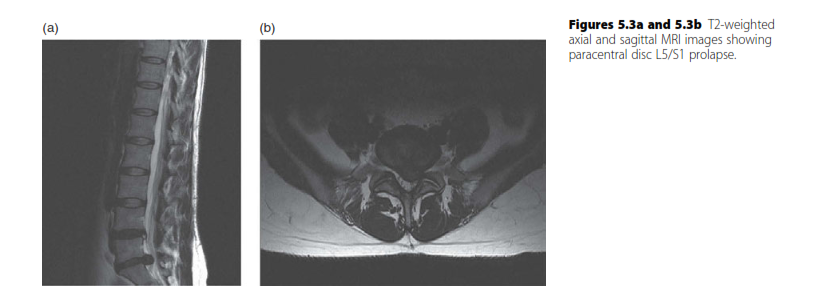

Spine structured oral questions3: The prolapsed intervertebral disc EXAMINER : A 37-year-old man has been ref…